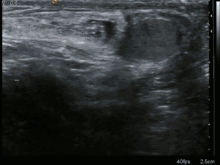

Une hernie inguinale est une protrusion pathologique d'une portion de péritoine[1] contenant éventuellement[1] des viscères abdominaux[1],[2] (il s'agit le plus souvent d'une partie de l'intestin grêle, parfois du gros intestin et, dans certains cas, de la vessie[3],[4],[5]) par le canal inguinal[3] (pour la hernie indirecte, qui est la plus fréquente[6]) ou directement par une ouverture des muscles abdominaux[3],[7] (pour la hernie directe), au travers de la paroi abdominale. Elle peut être congénitale ou acquise[8], et se manifeste par une tuméfaction sous-cutanée de l’aine.

Diagnostic

Chez l'homme, les orifices herniaires se palpent à travers les bourses, avec un doigt coiffé du scrotum.

Les hernies non étranglées sont réductibles, pas ou peu douloureuses et impulsives à la toux, tandis que les hernies étranglées ont les caractéristiques inverses et se présentent dans un tableau d'occlusion intestinale. Les hernies sont plus facilement décelables, le patient étant debout.